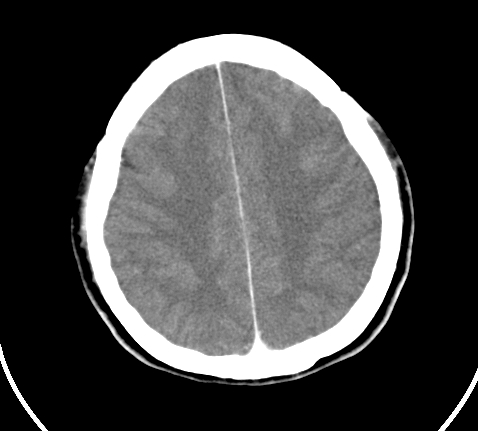

胸部